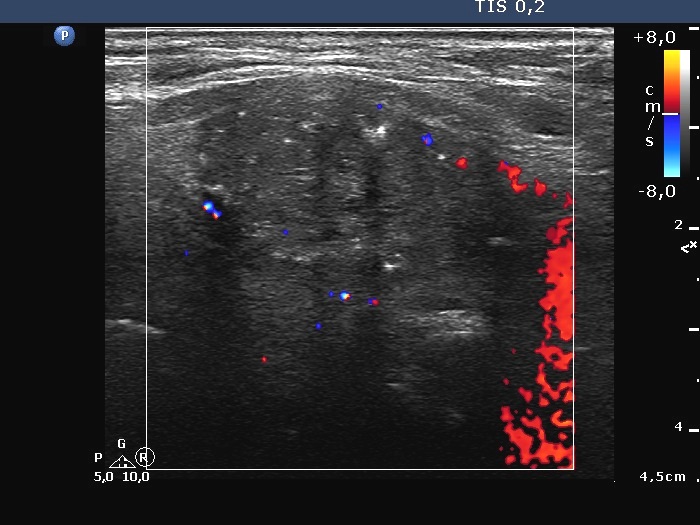

Ultrasonography. The thyroid was echonormal. A large hypoechoic nodule occupied almost the entire right lobe. The nodule showed various intranodular echogenic figures, including microcalcifications, macrocalcification and non-specific figures. The borders were indistinctive. The lesion was suspicious spreading extrathyroidal.